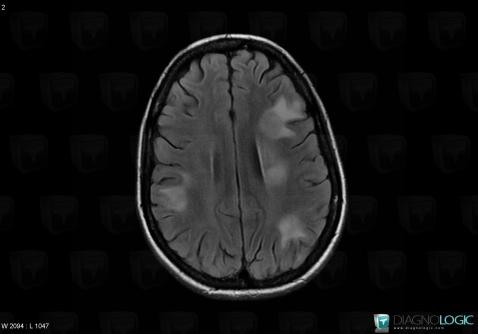

Toxoplasmosis, Cerebral hemispheres, MRI

Here is the specific information in the key image above:

- Diagnosis Toxoplasmosis (link to Abscess), Location(s) Cerebral hemispheres, with gamuts Intracerebral lesion with ring enhancement